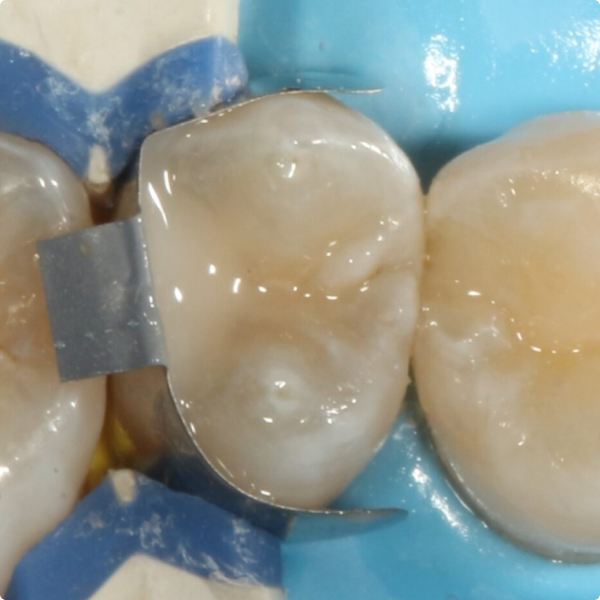

Although Stela can be used without a rubber-dam, Dr Shankla opted for one to maintain optimal isolation and control. After removing the decayed tissue, photographs were taken to document the cavity’s extent. A sectional matrix was placed to ensure proper contact, given the size of the lesion, then the Stela system was applied.

Stela simplifies the restoration process via a two-step protocol: first the primer (just 15 seconds), then the composite. The composite’s user-friendly consistency allowed sculpting before the material set, reducing procedural time and complexity.

The restoration was straightforward and efficient, taking less time than a traditional amalgam or multi-stage composite workflow. By using Stela, Dr Shankla reduced instrument use and the number of procedural steps making the treatment more cost- and time-effective. After placement, she allowed a few minutes for self-curing, then completed final trimming and polishing all without the need of a curing light.